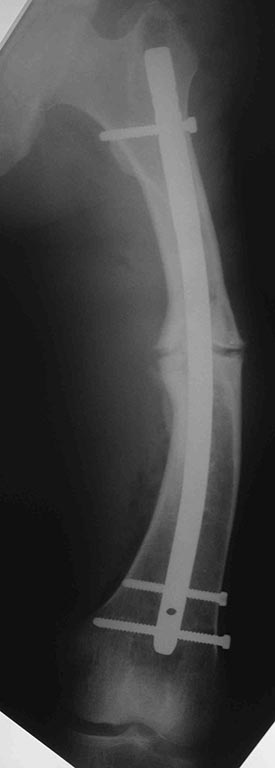

В травматологическом отелеении находится 16 летний юноша с

пателло-феморальным артрозом,

вторичной деформацией мыщелка бедра и надколенника.

Обратился с жалобами на боли в левом коленном суставе при ходьбе. В 2011

году находился на стационарном лечении в нашей кинике по поводу

застарелого перелома внутреннего края левого надколенника с разрывом

капсулы сустава, хондромаляции наружного мыщелка бедра и гемартроза. За

год до госпитализации перенёс двукратный спонтанный вывих левого

надколенника. В отделении (март 2011 года) выполнена артроскопия,

санация гиалинового хряща наружного мыщелка. Артропластика по Кемпбеллу.

Исходя из жалоб и результатов обследования, нами рассматривается

следующий вариант хирургической помощи больному. Надмыщелковая

остеотомия бедра, выполнение 15 градусов внутренней ротации дистального

сегмента, его варизирующее отклонение на 15 град. до исправления

вальгуса (анатомической оси конечности ). Очень сомневаемся в отношении

вмешательства на поддерживающем аппарате надколенника. Мнения

разделились: сделать латеральный релиз, либо не трогать совсем. Делать

ли дупликатуру медиального отдела капсулы? Вызывает опасения

неконгруентность суставной поверхности надколенника. Рассматриваем

вариант V-образной остеотомии надколенника. Следует ли ╚

подгонять ╩ такой надколенник по мыщелку или оставить в надежде на

постепенную перестройку.